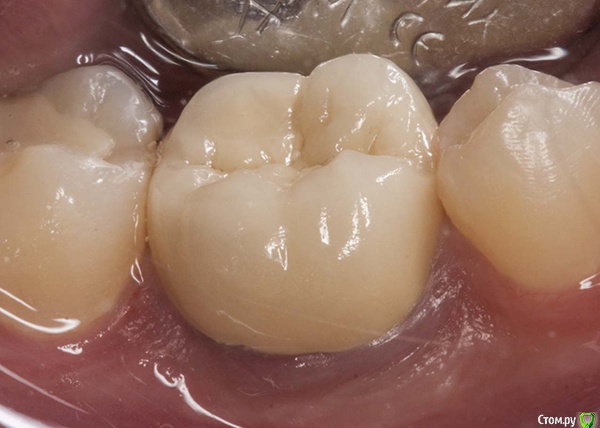

M@estro Опубликовано 23 июля, 2015 Автор Поделиться Опубликовано 23 июля, 2015 И сюда закину Жалобы на боли, КЕСТУ и желание " удалить " . Зуб 3.6 . Пациент - парнишка 16 лет. Зуб ранее пытались лечить,парень признался, что было больно, и больше он туда не вернулся, а в другой клинике предложили удалить зуб , ибо "кЕста". Перкуссия - резко-болезненна , в полости зуба - остатки ватки. В первое посещение - билд, обработка каналов ( дистальный 70/02 , медиальные 50 / 02) , антисептика, кальций на 2 недели . Второе посещение - обтурация , в дистальном -" неаккуратненько", плюнул силер. Следом бюджетная мк коронка. Контрольный через 4 месяца. 9 Ссылка на комментарий

M@estro Опубликовано 27 января, 2016 Автор Поделиться Опубликовано 27 января, 2016 Повторное эндо ( ре-колл 7 месяцев) . 5 каналов в 3.6 . Обтурация - CWCT . Мех.обработка - Profile + m2 . Ca(OH)2 на 2 недели 12 Ссылка на комментарий